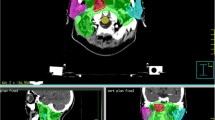

Figure 2 shows a schematic of transversal dose distributions in 1 treatment plan and 5 U-plans. The transversal dose coverage varies due to set-up uncertainty. To visualize the dose difference, a color wash schematic of differences in dose distributions is shown in Fig. 3. The maximum dose discrepancies were observed in marginal zones of PTVs. The dose changes of OARs were also greater in the vicinity of marginal zones and lesser distal to these areas.

The average dose difference was shown in Table 3. No obvious differences were found in D2cc. The mean dose differences of D98% and D95% of PTVp were respectively 3.30 Gy and 2.02 Gy. Decreased ΔD98% (1.12 Gy) and ΔD95% (0.58 Gy) were seen in CTVp. The ΔD98% and ΔD95% in GTVp were 0.56 Gy and 0.33 Gy, indicating that the CTV-to-PTV margin promoted the robustness of GTV and CTV. Similarly, the PTVn had the largest difference of D98% (2.77 Gy) and D95% (2.00 Gy). The ΔD98% and ΔD95% of CTVn were 1.39 Gy and1.03 Gy. Minor dose differences were observed in GTVn for both D98% (0.64 Gy) and D95% (0.59 Gy). No marked mean dose variations of Dmean were seen. Superior robustness in PTV and CTV was seen.

Table 4 showed the dose differences of OARs. The ΔDmax of the brain stem and PRV were 4.34 Gy (1.50 Gy-11.10 Gy) and 6.21 Gy (2.40 Gy-10.19 Gy). The ΔDmax of the spinal cord and PRV were 2.86 Gy (1.00 Gy-7.10 Gy) and 3.64 Gy (1.70 Gy-7.40 Gy). Narrowed width of DVH bands was observed in the bilateral lens. Optical nerves performed marked dose difference of mean dose, which were 8.00 Gy, 8.66 Gy, and 8.81 Gy for optical nerve L,R, and chiasma. The Dmean of bilateral parotid glands exhibited obvious changes.

A sample of dose-volume histograms (DVHs) of PTVs, CTVs, and GTVs was shown in Fig. 4. The solid line represented the DVH of the treatment plan, and the 5 dashed lines represented the DVH of U-plans. The envelope was defined as the area between all the DVH curves. The gradually narrowed envelope was seen in PTVp (Fig. 4A), CTVp (Fig. 4D), and GTVp (Fig. 4G). PTVn (Fig. 4B) exhibited high sensitivity to set-up uncertainty. Narrowed width of the envelope was seen in CTVn (Fig. 4E). Sufficient dose coverage and decreased robustness were noticed in GTVn (Fig. 4H). Superior robustness was seen in PTV (Fig. 4C) and CTV (Fig. 4F).

As to OARs (Fig. 5), the brain stem (Fig. 5A) and its PRV (Fig. 5B) exhibited weak robustness due to their locations in the vicinity of PTVs. The spinal cord (Fig. 5C) and its PRV (Fig. 5D) had stronger robustness. Bilateral parotid glands (Fig. 5E. F) were sensitive to set-up uncertainty for their being partially enclosed PTVs. The Dmax of bilateral optical nerves (Fig. 5G–I) and lens(Fig. 5J, K) varied slightly.